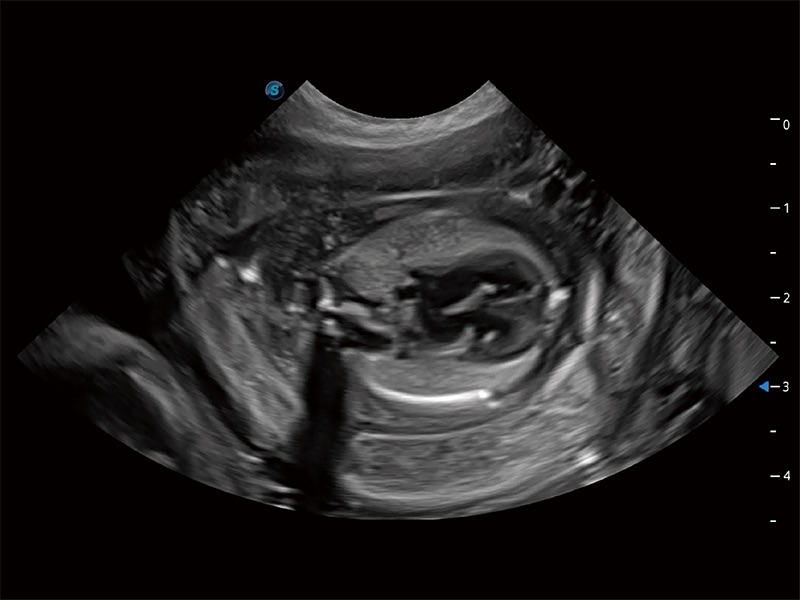

高性能和先進(jìn)的臨床應(yīng)用工具可以為動物醫(yī)生提供臨床信心。ProPet 80 搭載了先進(jìn)的腹部和淺表應(yīng)用工具,幫助醫(yī)生在日常臨床實(shí)踐中發(fā)揮前所未有的作用。

極大提升超低速微細(xì)血流的檢出能力,同時更精準(zhǔn)地濾除軟組織和超聲信號,為獸用醫(yī)生提供以往無法通過常規(guī)血流獲得的疾病診斷信息。

在傳統(tǒng)二維血流成像的基礎(chǔ)上,呈現(xiàn)血流的立體感,具有動感的生命力之美。即便是微小的血管也能輕松應(yīng)對,提高了血流的視覺敏感性。

操作簡便,無需高頻度外力作用即可真實(shí)反映組織的形變,快速評估腫瘤良惡性。

非線性融合造影成像充分利用諧波和基波信號,為難以觀察的血流進(jìn)行增強(qiáng)顯像??捎糜诰€陣、凸陣、微凸陣、相控陣探頭。